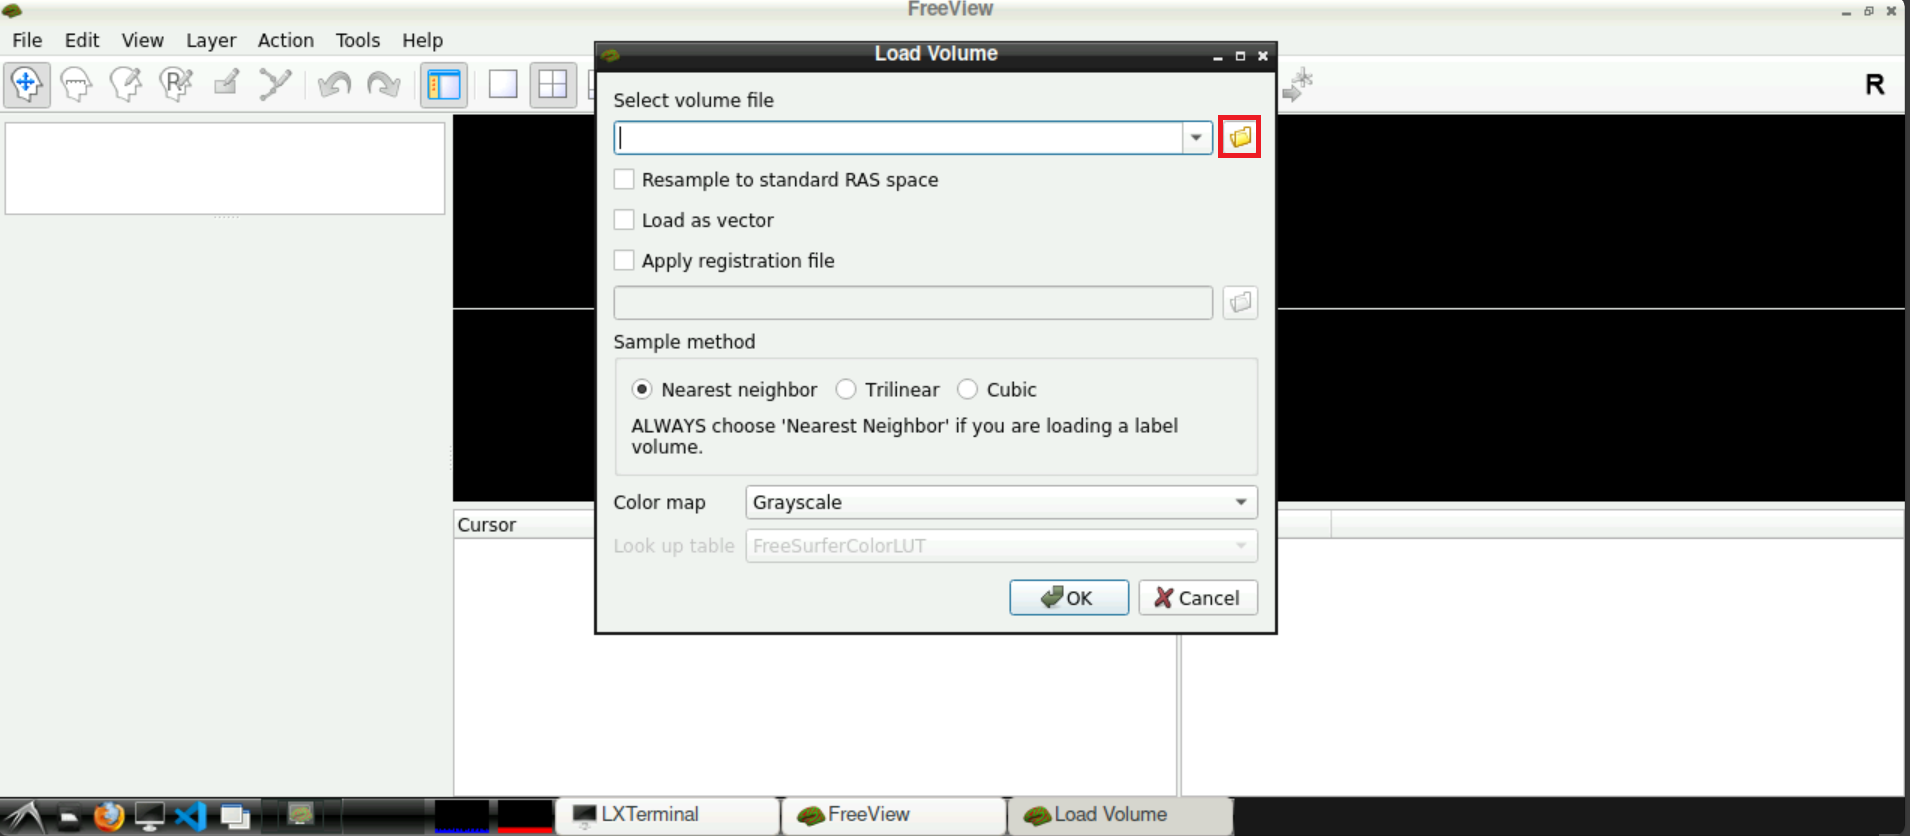

For this, select File > Load Volume (top left corner in freeview):

A new window opens, asking you to Select volume file. Either type in the path(s) to your/a functional scan manually, or start by clicking on the folder symbol